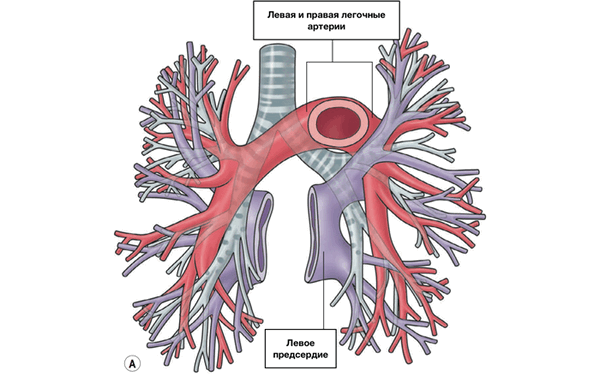

Сосуды легких

Легочный ствол (truncus pulmonalis) диаметром 30 мм выходит из правого желудочка сердца, от которого он отграничен своим клапаном. Начало легочного ствола и соответственно его отверстие проецируются на переднюю грудную стенку над местом прикрепления хряща III левого ребра к грудине. Легочный ствол расположен кпереди от остальных крупных сосудов основания сердца (аорты и верхней полой вены). Справа и позади него находится восходящая часть аорты, а слева прилежит левое ушко сердца. Легочный ствол, находящийся в перикардиальной полости, направляется впереди аорты влево и кзади и на уровне IV грудного позвонка (хряща II левого ребра) делится на правую и левую легочные артерии. Это место называется бифуркацией легочного ствола (bifurcаtio tninci pulmonalis). Между бифуркацией легочного ствола и дугой аорты расположена короткая артериальная связка(ligamentum arteriosum), представляющая собой заросший артериальный (боталлов) проток (ductus arteriosus).

Правая легочная артерия (a.pulmonаlis dextra) диаметром 21 мм следует вправо к воротам правого легкого позади восходящей части аорты и конечного отдела верхней полой вены и кпереди от правого бронха. В области ворот правого легкого впереди и под правым главным бронхом правая легочная артерия разделяется на три долевые ветви. Каждая долевая ветвь в соответствующей доле легкого в свою очередь делится на сегментарные ветви. В верхней доле правого легкого различают верхушечную ветвь (r.apicаlis), задние нисходящую и восходящую ветви (rr.posteriores descendens et ascendens), передние нисходящую и восходящую ветви(rr.anteriores descendens et ascendens), которые следуют в верхушечный, задний и передний сегменты правого легкого.

Ветвь средней доли (rr.lobi medii) делится на две ветви — латеральную и медиальную (r.lateralis et r.mediаlis).

Эти ветви идут к латеральному и медиальному сегментам средней доли правого легкого. К ветвям нижней доли (rr.lobi inferioris) относятся верхняя (верхушечная) ветвь нижней доли [r.superior (apicаlis) lobi inferioris], направляющаяся к верхушечному (верхнему) сегменту нижней доли правого легкого, а также базальная часть(pars basаlis). Последняя делится на 4 ветви: медиальную, переднюю, латеральную и заднюю (rr.basаles mediаlis, anterior, laterаlis et posterior). Они несут кровь в одноименные базальные сегменты нижней доли правого легкого.

Левая легочная артерия (a.pulmonаlis sinistra) короче и тоньше правой, проходит от бифуркации легочного ствола по кратчайшему пути к воротам левого легкого в поперечном направлении впереди нисходящей части аорты и левого бронха. На своем пути артерия перекрещивает левый главный бронх, а в воротах легкого располагается над ним. Соответственно двум долям левого легкого легочная артерия делится на две ветви. Одна из них распадается на сегментарные ветви в пределах верхней доли, вторая — базальная часть — своими ветвями кровоснабжает сегменты нижней доли левого легкого.

К сегментам верхней доли левого легкого направляются ветви верхней доли (rr.lobi superioris), которые отдают верхушечную ветвь(r.apicаlis), передние восходящую и нисходящую (rr.anteriores ascendens et descendens), заднюю (r.posterior) и язычковую(r.lingulаris) ветви. Верхняя ветвь нижней доли (r.superior lobi inferioris), как и в правом легком, следует в нижнюю долю левого легкого, к его верхнему сегменту. Вторая долевая ветвь — базальная часть (pars basаlis) делится на четыре базальные сегментарные ветви: медиальную, латеральную, переднюю и заднюю (rr.basаles mediаlis, laterаlis, anterior et posterior), которые разветвляются в соответствующих базальных сегментах нижней доли левого легкого.

В ткани легкого (под плеврой и в области дыхательных бронхиол) мелкие ветви легочной артерии и бронхиальных ветвей, отходящих от грудной части аорты, образуют системы меж- артериальных анастомозов. Эти анастомозы являются единственным местом в сосудистой системе, в котором возможно движение крови по короткому пути из большого круга кровообращения непосредственно в малый круг.

На рисунке представлены артерии, соответствующие сегментам легких.

ЛЕГОЧНЫЕ ВЕНЫ

Из капилляров легкого начинаются венулы, которые сливаются в более крупные вены и в каждом легком формируют по две легочные вены.

Из двух правых легочных вен больший диаметр имеет верхняя, так как по ней оттекает кровь от двух долей правого легкого (верхней и средней). Из двух левых легочных вен больший диаметр имеет нижняя вена. В воротах правого и левого легких легочные вены занимают их нижнюю часть. В задней верхней части корня правого легкого расположен главный правый бронх, кпереди и книзу от него — правая легочная артерия.

У левого легкого сверху находится легочная артерия, кзади и книзу от нее — левый главный бронх. У правого легкого легочные вены лежат ниже артерии, следуют почти горизонтально и на своем пути к сердцу располагаются позади верхней полой вены, правого предсердия и восходящей части аорты. Обе левые легочные вены, которые несколько короче правых, находятся под левым главным бронхом и направляются к сердцу также в поперечном направлении, кпереди от нисходящей части аорты. Правые и левые легочные вены, прободая перикард, впадают в левое предсердие (их конечные отделы покрыты эпикардом).